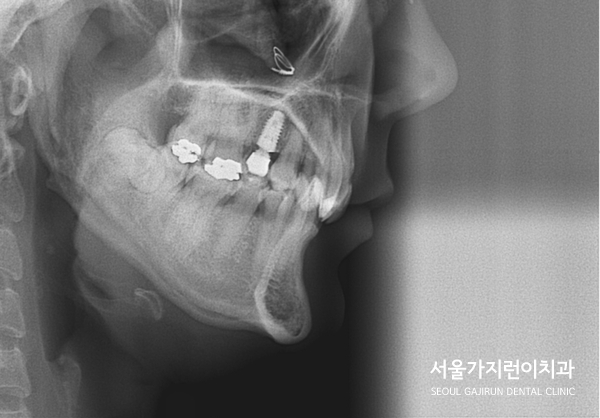

문제는 상악 우측 제1대구치에 임플란트를 식립한 환자라는 점입니다.

임플란트는 교정력이 있어도 이동하지 않으며 이 부분에 힘이 가해질 경우

임플란트의 파손으로 이어질 수 있어 상당한 주의가 필요한데요.

임플란트의 존재와 임플란트 주변의 치아 이동에 제한이 있기 때문에

꼼꼼한 교정플랜이 뒷받침되어야 했습니다.

상기 환자분의 경우 임플란트 치아가 움직이지 않도록 최대한 노력하였으며

다행히도 임플란트 이상 없이 교정력을 유지하면서 치아교정을 마무리할 수 있었습니다.